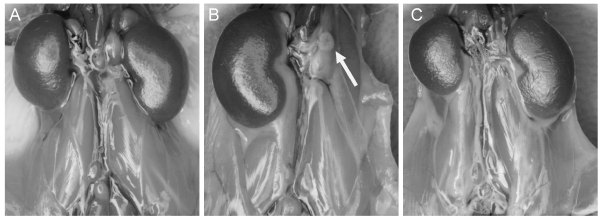

由张锋教授领导的这项研究利用全外显子组测序和CGH芯片方法,从中国和美国的多中心病例样本中鉴定到102例16p11.2/TBX6缺失的携带者,通过回顾临床数据,发现25%的亚裔突变携带者和16% 的高加索裔/西班牙裔突变携带者有先天性肾脏和尿路畸形(图1)。这个患病比例远高于普通人群中1/1000的先天性肾脏和尿路畸形比例。同时,该研究团队回顾了7例TBX6基因点突变携带者的临床数据,发现其中4例是先天性肾脏和尿路畸形患者,存在肾脏发育不全等问题。然后,该团队利用CRISPR基因编辑技术建立了一系列具有不同Tbx6基因表达水平的突变小鼠模型,并对小鼠肾脏表型进行深入分析,明确了小鼠Tbx6基因缺陷会导致肾脏发育的异常(图2)。随着Tbx6基因表达量降低,小鼠肾脏发育异常的风险也随之升高。该研究成果可以为先天性肾脏和尿路畸形的分子诊断、遗传咨询和临床干预提供新的理论指导。